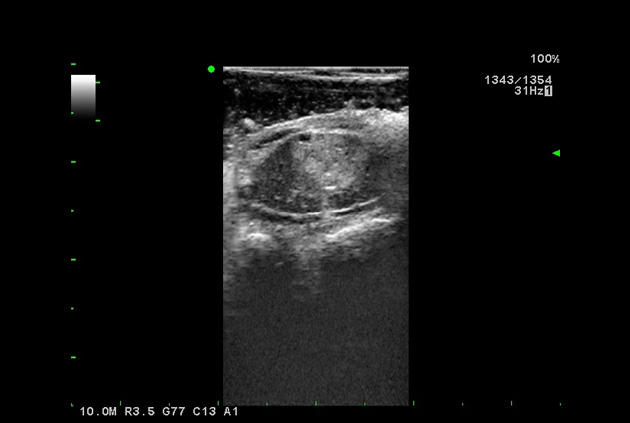

Giving the surgeon complete control

The Fujifilm Healthcare transducer utilizes the full benefits of the Wrist Articulation™ of the robotic instruments to capture real-time ultrasound imaging even at complex angles and difficult-to-reach areas.

Our smallest footprint allows for enhanced contact in tight spaces

Our newest probe, the L51K allows the surgeon access to difficult-to-reach areas that no other probe on the market can go. The unique design and proximal location of the attaching mechanism provides full wrist articulation and easier grasp and release.

The next level in Robotic Ultrasound

Full wrist articulation with optimized functional length.

A critical function of robotic ultrasound guidance is tumor margin identification. Fujifilm's family of robotic probes all have the optimum location of the attaching mechanism that allows for full wrist articulation of the probe. The result is an increased confidence that the tumor margins have been completely identified.